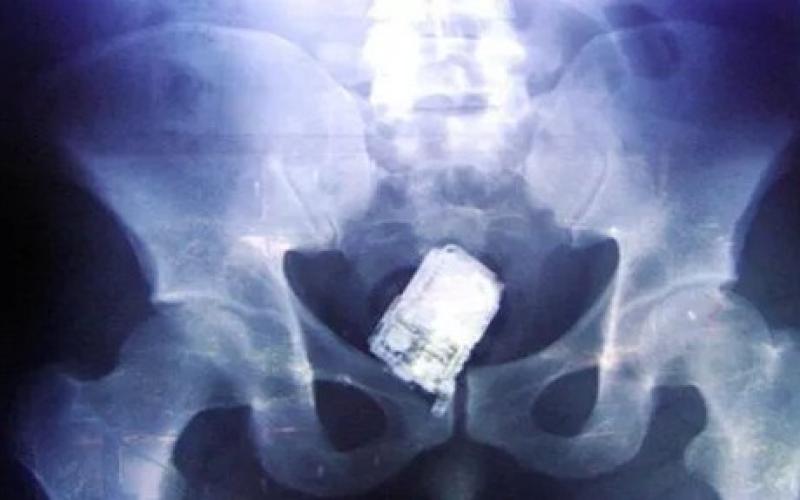

نفى وزير الصحة الدكتور سعد جابر صحة فيديو وخبر مفبرك يشير الى نسيان احد الاطباء هاتفه في بطن مريضة .

وقال جابر ان الفيديو تم تداوله عام 2015 وتم نفيه أنذاك لعدم صحته. وقال: ان وزارة الصحة نفت الحادثة عام 2015 واوضحت ان المريضة المقصودة كانت قد اجري لها عملية قيصرية بنيسان 2015، في احد المستشفيات العامة وبعد اسبوعين من العملية راجعت المستشفى نتيجة الام كانت تعاني منها .

واشارت الوزارة بتوضيحها انه بفحص وتصوير المريضة تبين ان الالام التي كانت تعاني منها ناتجة عن التهاب جرح العملية وقد تم ادخالها المستشفى على الفور والمباشرة في علاجها وخرجت من المستشفى بعد اتمام العلاج معافاة لا تعاني من اي مضاعفات .